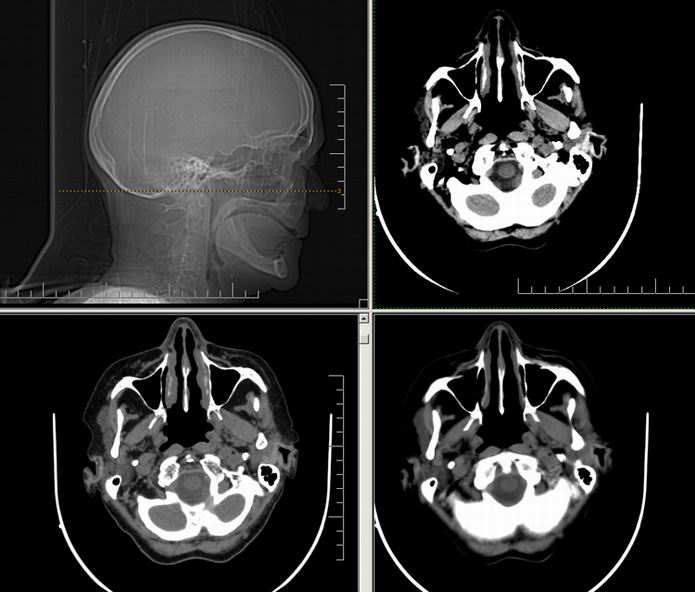

Est ce que qqun a des coupes axiales de crâne pour m'aider à réviser mon anatomie. Merci

Pour compléter tes révisions, Poupette vient de nous faire parvenir ces planches bien utiles: Planches de coupes axiales cérébrales, dans la rubrique COURS / ANATOMIE